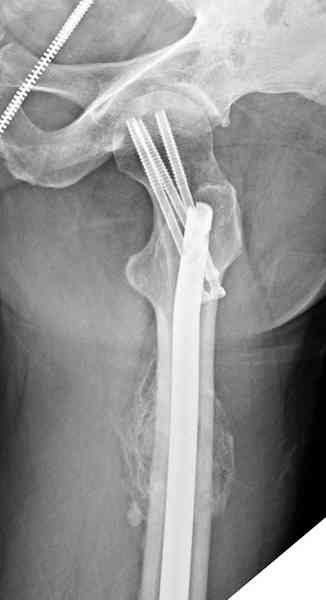

Перелом шейки бедра, выявленный после штифтования диафиза |

С наступающим Новым 2007 годом! Желаю успехов в работе, здоровья вам, родным и близким.Оперировали диафизарный перелом бедра у тяжелого больного(после АРО, с анемией, с нарушениями свертывания). Снимка В\3 бедра до операции не было, штифт пробит ретроградно без проблем. После операции: гемоглобин 86, прошло 6 дней. Смущала отечность в В\3 бедра, на рентгенограмме вот такая "новость". Как выйти из этой ситуации? Вытащить штифт, посадить пластину на С\3, а на В\3 углообразную пластину после коррекции (остеотомии) не позволяет состояние больного. А есть смысл ввести мимо штифта компрессирующие винты под рентген-контролем? Ваши предложения? Заранее благодарю.

Даже если бы и позволяло состояние больного, делать этого ни в коем случае не надо. Какая коррекция (остеотомия)??? Перелом шейки очень латеральный, практически без смещения, кровообращение головкт бедра не должно было пострадать, возраст, судя по всему, - молодой... Хорошие перспективы для сращения шейки.

Диафизарный перелом простой опорный - должен срастись и на таком неблокруемом гвозде (если туго посажен в рассверленный канал).

Именно так и надо сделать!!! Сейчас, в этом году, пока непоздно!

Согласен с Алексеем, это в сложившейся ситуации безальтернатиный вариант.

Диафизарный перелом низковат для остеосинтеза без запирающих винтов, может, пару винтов провести по обе стороны стержня, чтобы "сузить" канал в периферическом оломке.

Приблизительно 5-7% переломов бедра сопровождаются переломом шейки.

В операционной спереди гвоздя провел два 6.5 мм каннулированных шурупа, также через проксимальное отверстие антеградного гвоздя удалось провести шуруп.

При "ipsilateral femoral shaft and neck fractures" пользуемся ретроградным штифтом до малого вертеля, а шейку фиксируем каннюлированными шурупами в 6.5 или 7.3 мм в зависмости от диаметра шейки.

Здесь представлены снимки больного 65 лет, поступившего с диагнозом перелом

бедра после автоаварии.

В первый же день произведено антеградное штифтованием DePuy Trochanteric Nail.

На второй день (7) обнаружен пропущенный перелом,

сделаны Компьютерная Томограмма

и проведены шурурпы через и спереди штифта без удаления.

Послеоперационные снимки